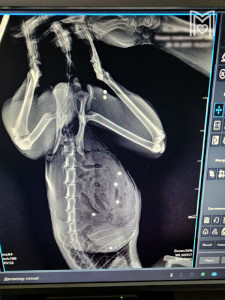

Арестована хозяйка пыточного рехаба из подмосковного Дедовска Анна Хоботова. Ранее она пыталась скрыться от следствия. На допросе она не признала вину и не раскаялась. Ранее мы писали, что в Дедовске действовал рехаб, в котором избивали, унижали и всячески издевались над детьми.

О нём стало известно благодаря врачам одной из больниц, куда в критическом состоянии привезли 16-летнего парня по имени Рома. Он до сих пор находится в коме после издевательств в центре.

Против Хоботовой возбуждены уголовные дела по статьям «Истязание несовершеннолетних», «Незаконное лишение свободы» и «Оказание услуг, не отвечающих требованиям безопасности».